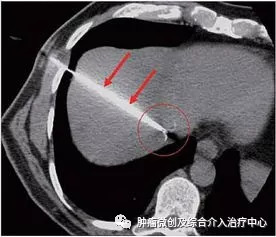

肝癌的治疗中还有一种方法,叫做消融,就是用一根会发热的电极,放到肝癌里面将肿瘤“烧”死。

射频消融(RFA):RFA的治疗原理是利用高频电流(375~500kHz)通过针状电极与接地板在体内形成回路,交替电流的激发引起电极周围组织离子高频振动,相互碰撞摩擦产生热能,局部组织温度升高,蛋白质变性,从而导致组织不可逆凝固性坏死,达到杀死肿瘤细胞的目的。病变凝固坏死的“理想”温度约为60-65℃,但电极尖部周围的组织可吸收热量,因此必须加热到高于理想温度才能达到治疗目的。然而,温度>100℃可引起组织脱水和炭化,导致阻抗增加,从而阻止能量的进一步沉积,因此最佳治疗温度约为85-90℃。